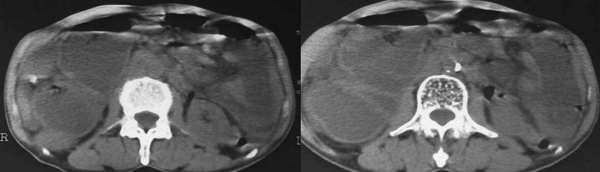

以下是引用lkc8963在2006-1-19 21:13:00的发言:[br]右半结肠及盆腔小肠明显积液扩张,腹腔内无明显渗出;右半结肠近端见多发点状高密度影;胆管内多发结石。[br]不知临床有哪些资料。本例需考虑胆石性肠梗阻的可能性,或胆系结石漏至结肠(异常通道如瘘)。

以下是引用wawaquan在2006-1-19 23:55:00的发言:[br]胆系结石,右半结肠梗阻:考虑横结肠占位(横结肠壁厚呈肿块状)。